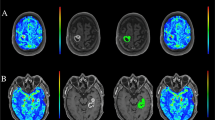

Axial FLAIR images were transferred to the same voxel space and co-registered to DCE and DSC images, respectively, using SPM8 (MathWorks, Natick, MA). All ROIs were manually delineated on the FLAIR images using an in-house developed MatLab-based software and transferred to the perfusion maps (Fig. 1a, b). The tumour ROI was delineated just inside its border, on all slices with high FLAIR signal by a resident in radiology (3 years of experience) blinded to histopathological diagnosis. Tumour delineation was performed on all co-registered FLAIR slices with suspected tumour changes that had a corresponding perfusion slice on DCE and DSC, respectively. A ROI in the normal appearing white matter was delineated in the lobe contralateral to the tumour area in one slice.

Histogram parameters from the DCE and DSC perfusion scans were compared between grade II and III gliomas.

For DCE, the perfusion parameter skewness of k trans had the lowest p value for separating glioma grades II and III (p = 0.07). Histogram perfusion parameters from DCE for glioma grades II and III are presented in Table 2.

For DSC, the standard deviation of CBF had the lowest p value and showed significant difference between glioma grade II and glioma grade III (p = 0.02). Histogram perfusion parameters from DSC for glioma grades II and III are presented in Table 3.